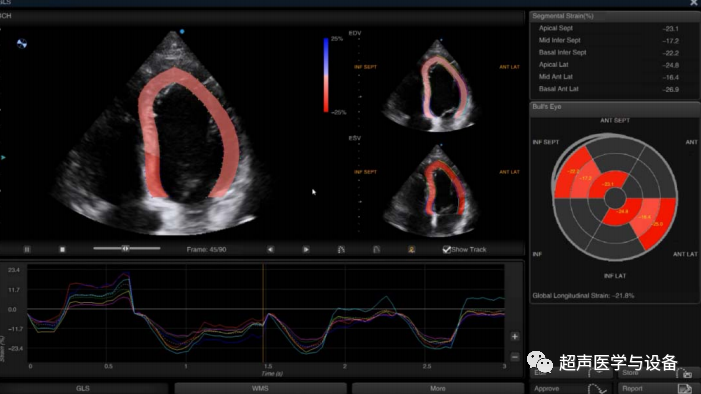

智能心肌运动性能定量评估 Auto SG

此外,在心脏功能及心肌定量诊断方面,SIUI的智能心肌运动性能定量评估功能能自动描迹心内膜和追踪心肌运动,获取左心室整体和节段心肌功能测量值;

▶ 提供多功能曲形图以及 17 节段的牛眼图显示 GLS 及 WMSI;

获取左心室整体纵向应变(GLS)和左心室室壁运动评分指数(WMSI)等数

据,用于评估左心室整体及局部功能;

可重复性高